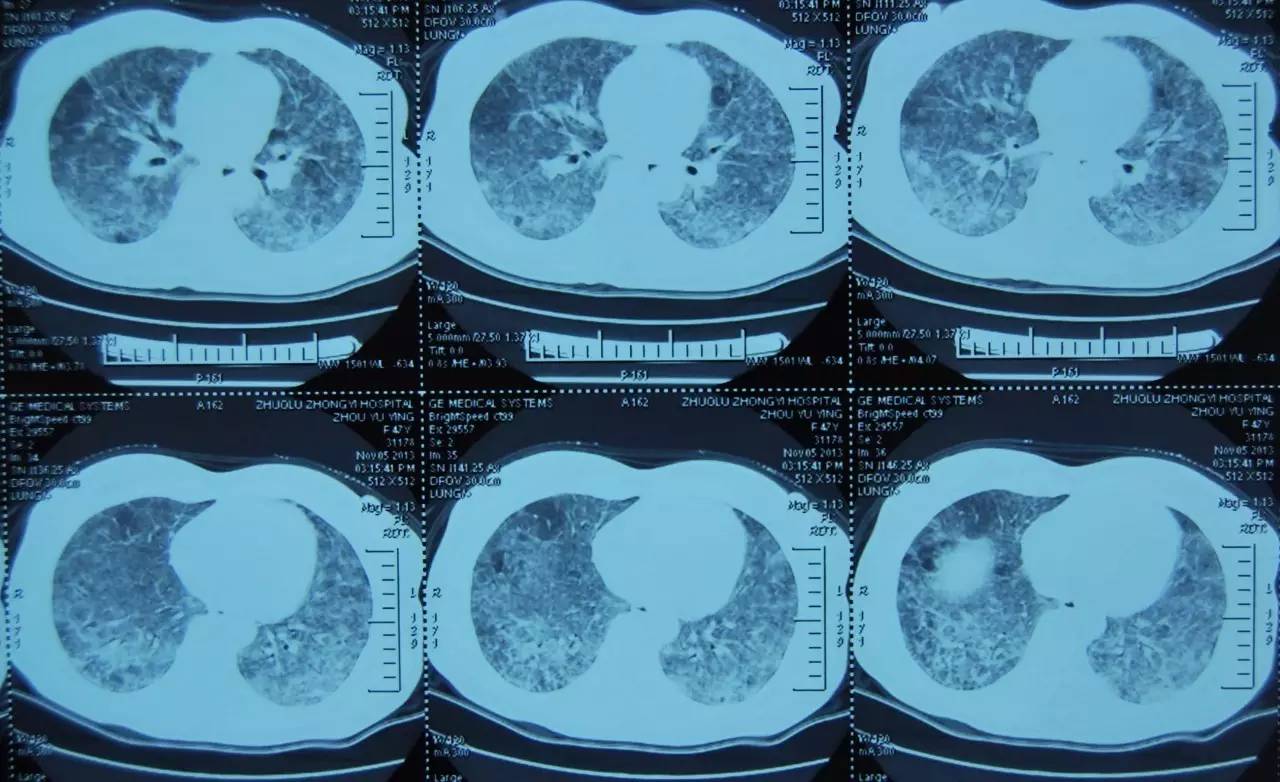

2013-11-20复查胸部CT提示双肺斑片影较前吸收(图1-图2),于2013-12-05出院,出院后服用醋酸泼尼松片 8mg 1次/日。患者仍喘息明显,日常生活不能自理。

图 1:2013年11月胸部CT

注:双肺弥漫性磨玻璃影及斑片影、可见空气潴留征及小结节影

图 2:2013年11月胸部CT